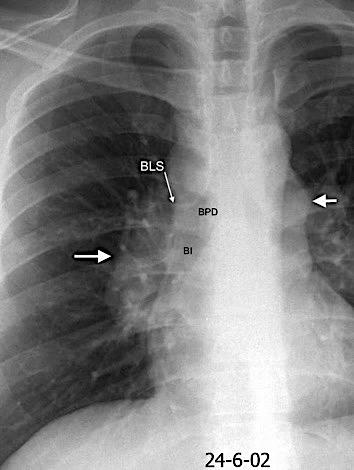

Anatomía

BPI: 75% de normales

La imagen es probable que represente al BPI, a la altura del nacimiento del BLSI.

AV,. The left lateral radiograph of the chest. Part One. Med. Radiogr. Photogr.1979.

La presencia de tumor o ganglios rodeando el BPI hace que este aparezca como mucho más nítido y definido.

Carcinoma microcítico..

Parálisis frénica. Atelectasia parcial de LSI.

Whitten CR. A Diagnostic Approach to Mediastinal Abnormalities. Radiographics 2007 / Marano R et al. Cardiac Silhouette findings And mediastinal lines and stripes. Chest. 2011

En el normal, el bronquio intermediario (BI) aparece en la proyección lateral, como una línea fina vertical que cruza el bronquio del LSI en su unión con el principal. (BPI) Engrosamiento del bronquio intermediario (BI)